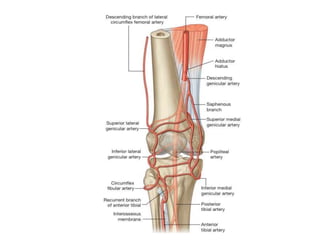

Can be done open or arthroscopy procedure ( now a days arthroscopic

release preferred )

Complications

1)Extending the release too far can cause medial subluxation of the

patella; infact medial patella subluxation or dislocation is almost always

iatrogenic, secondary to an overzealous lateral release.

2)injury to superolateral geniculate vessel to prevent this make a

superior anterolateral 2cm incision starting just lateral to the proximal

pole of patella.

Results varied, good results in short term(metcalf,Simpson),poorer in

long term(Christensen)